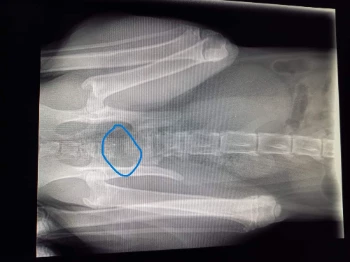

- meerdere foto's die moesten genomen worden.

- breuk aan de onderkant van zijn rug

- blaas was zeer ernstig beschadigd en werkte niet meer zelfstandig en diende om de 2u handmatig geledigd te worden.